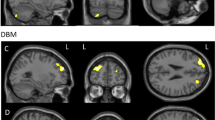

Voxel-wise modified TBSS analysis

Table 4 shows the results of the whole brain voxel-wise analysis. The pairwise group differences show a significant decrease in FA in the BC + SYST group vs. the NC group in a large number of voxels. Figure 4 shows a widespread bilateral distribution of affected white matter regions with a posterior dominance. Involved tracts include bilateral superior longitudinal fasciculus (SLF), bilateral sagittal stratum, bilateral posterior thalamic radiation, bilateral cingulum, bilateral corticospinal tract, bilateral corona radiata, splenium and body of the corpus callosum. For the BC-SYST vs. NC contrast, we also found a decrease in FA, albeit in a much lower number of voxels. Affected regions included left SLF, left corticospinal tract, left corona radiata, splenium of corpus callosum. At our predetermined threshold of p < .05 (TFCE, FWE corrected) we did not find significant group differences in decline in FA between BC + SYST and BC-SYST. When inspecting the results at a p < .001 uncorrected, however, we observed some small foci including bilateral SLF, indicating a steeper decrease of FA in these regions in the BC + SYST than the BC-SYST group. Few significant differences were found with regard to MD. The BC + SYST vs. NC comparison showed a significant decrease in MD in BC + SYST relative to NC in the body of the corpus callosum. When directly comparing BC + SYST vs. BC-SYST at an uncorrected p < .001 we found a steeper decrease in MD for BC + SYST than BC-SYST in the left sagittal stratum and left retrolenticular part of the internal capsule.

Results from voxel-wise modified TBSS analysis of FA maps. Effects show a decrease in FA from M1 to M2. BC + SYST < NC: more decrease in patients exposed to chemotherapy ± endocrine treatment vs. no cancer controls; BC-SYST < NC: more decrease in cancer patients not exposed to systemic treatment vs. no cancer controls; BC + SYST < BC-SYST: more decrease in patients exposed to chemotherapy ± endocrine treatment vs. cancer patients not exposed to systemic treatment. Analyses are TFCE corrected at p < .05 except for the BC + SYST < BC-SYST contrast. Significant effects are overlaid on the average FA of all participants. Statistical analyses were performed in native space. For visualization and anatomical reference, results were warped to MNI space

Moreover, our voxel-wise analysis showed a widespread reduction in FA from baseline to 6 months after chemotherapy when compared to the NC group (women without a cancer diagnosis). Affected white matter regions were largely bilaterally and somewhat posteriorly localized, including SLF, posterior thalamic radiation, cingulum, corticospinal tract, corona radiata and the splenium and body of the corpus callosum. These regions overlap with those previously reported in the longitudinal study by Deprez and coworkers (Deprez et al. 2012) who also did not skeletonize their data and used in-house developed registration algorithms to warp individual FA maps to a study-specific FA template (T1 scans were not used). A follow-up study to Deprez et al. (Billiet et al. 2018) observed a return to baseline values of FA 3 to 4 years after chemotherapy, suggesting recovery of white matter integrity after initial injury. Application of a skeletonization step might also explain the absence of voxel-based decline in FA in other studies in the field of CRCI (Chen et al. 2019; Correa et al. 2016; Mo et al. 2017).